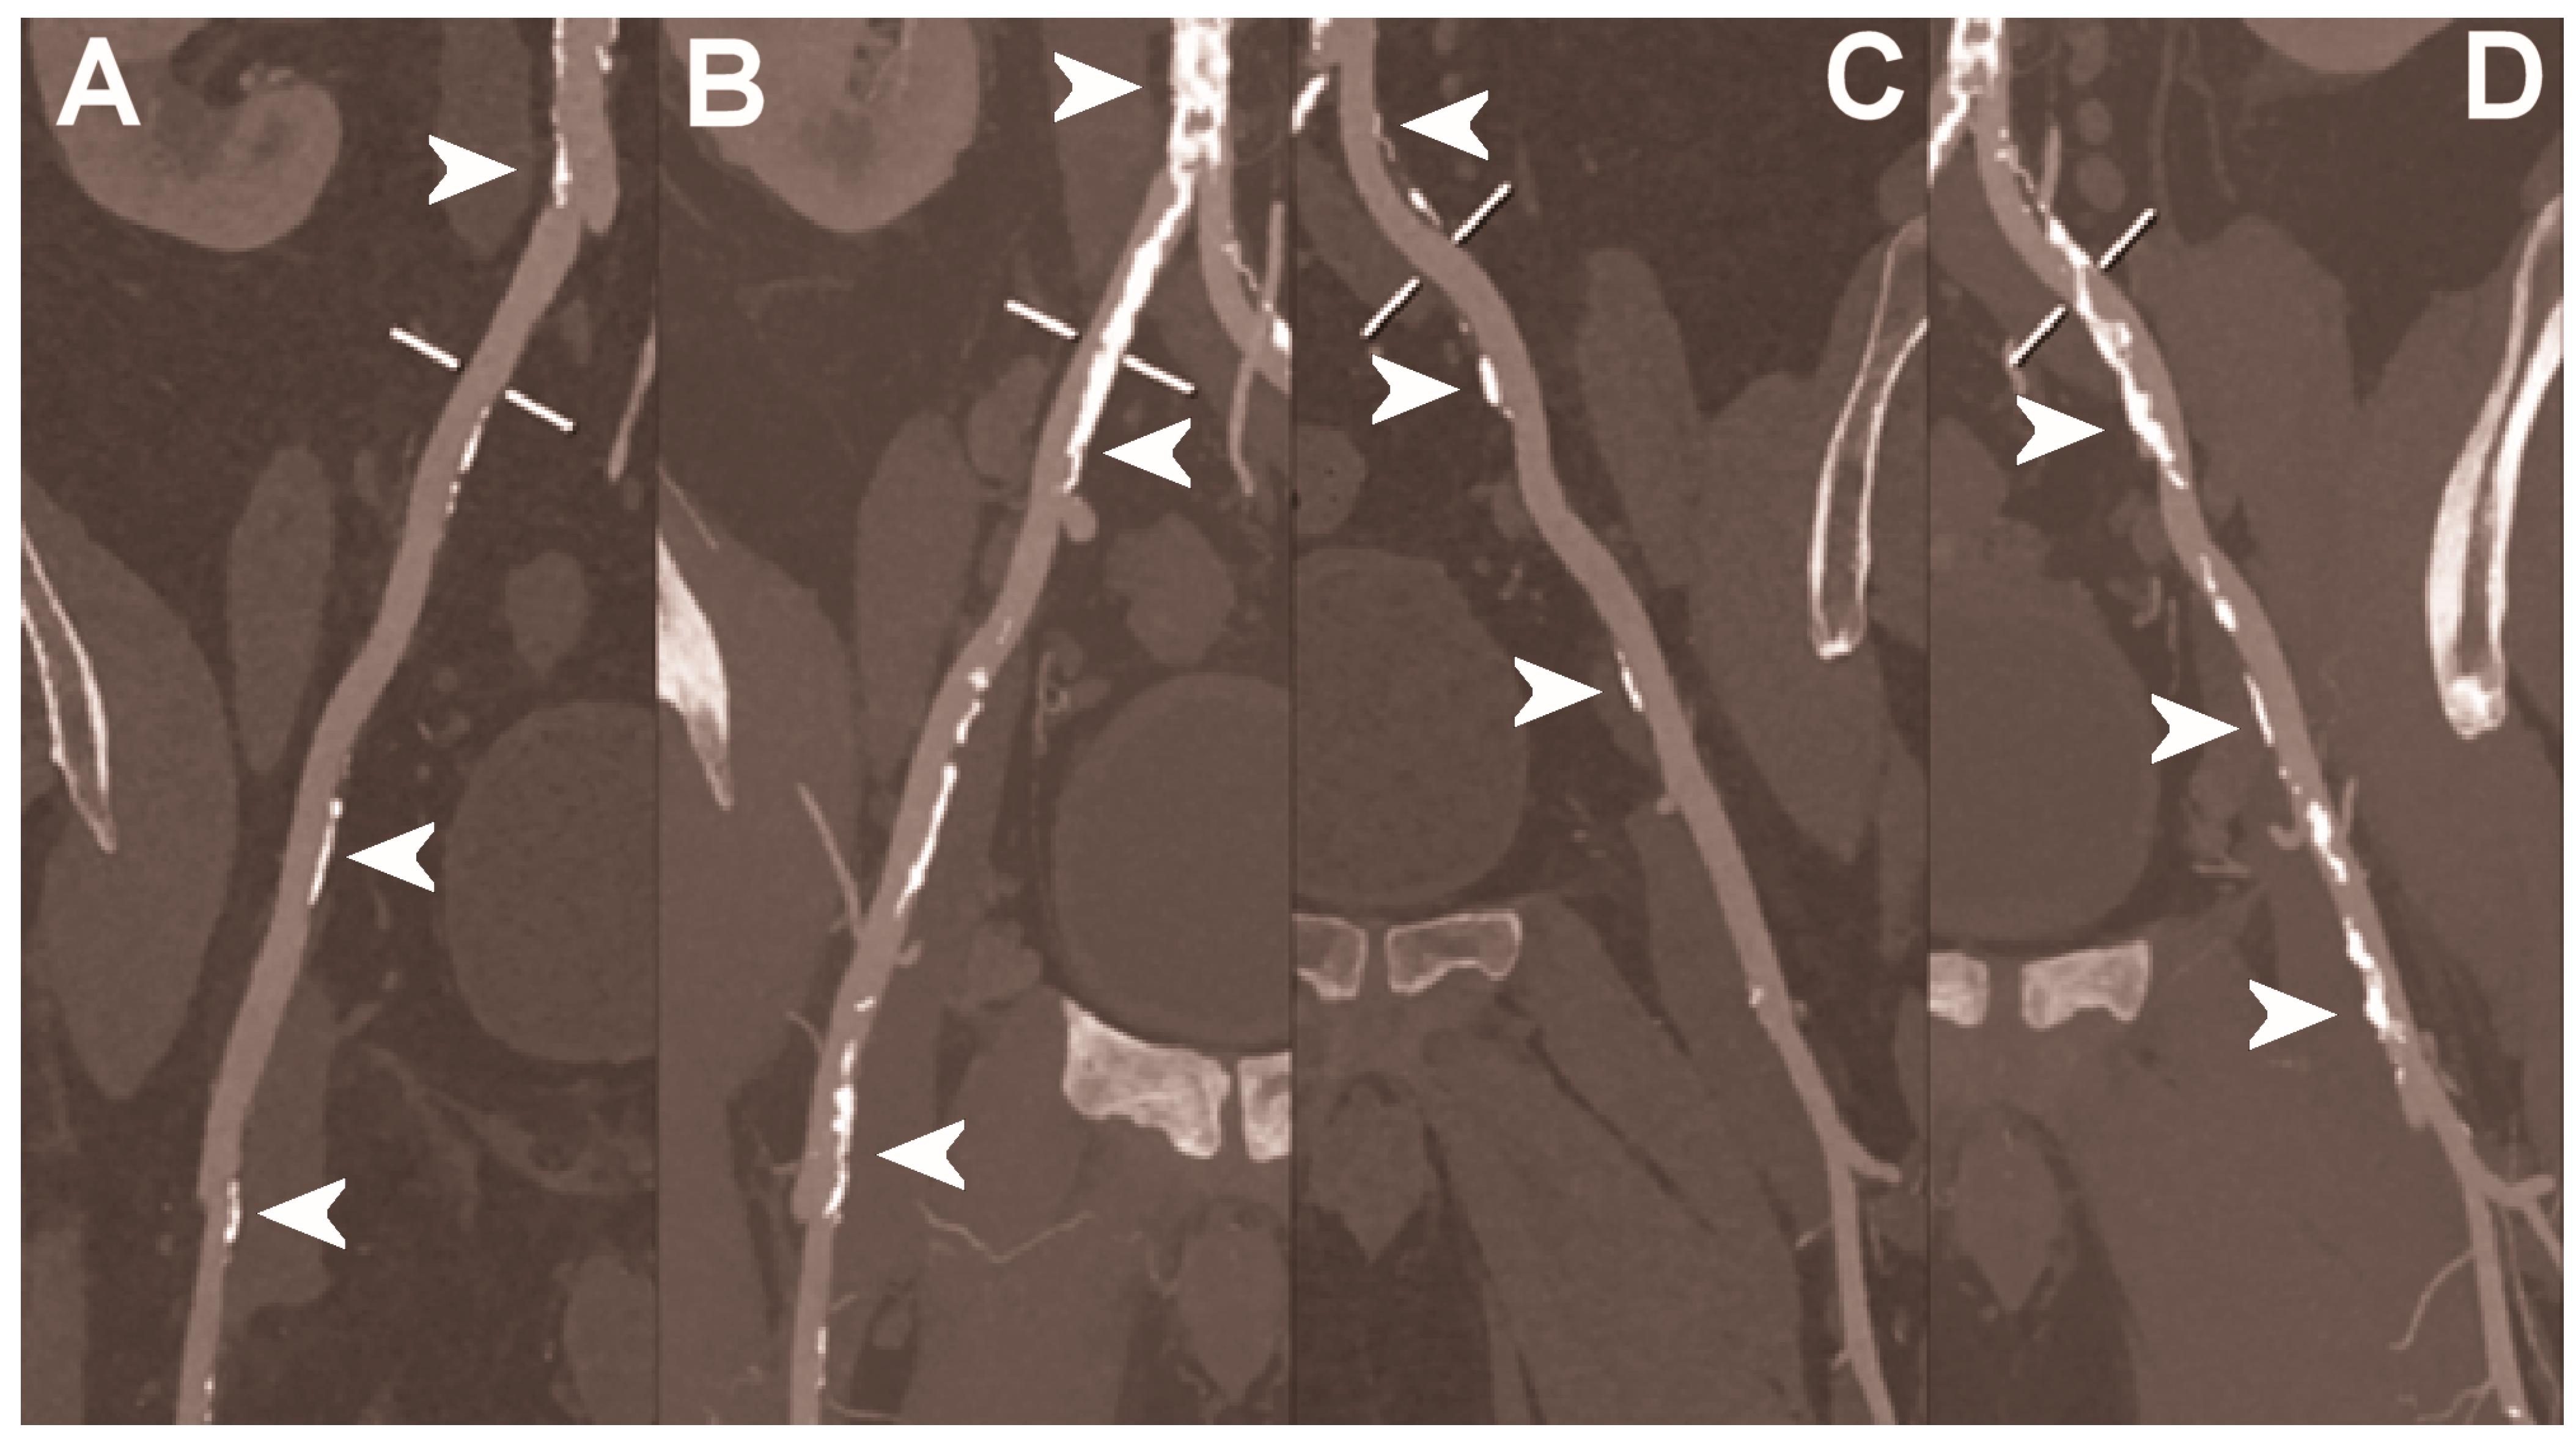

| Dangelmaier et al. 2018 [111] | In vitro phantom (abdominal aortic aneurysm phantom filled with iodine, gadolinium, or calcium). | Ability of PCCT in combination with a dual contrast agent injection to capture endoleak dynamics and effectively distinct leaking contrast media from intra-aneurysmatic calcifications, thereby allowing for a significant reduction of radiation exposure. |

| Sigovan et al. 2019 [112] |

|

|

- Dangelmaier, J.; Bar-Ness, D.; Daerr, H.; Muenzel, D.; Si-Mohamed, S.; Ehn, S.; Fingerle, A.A.; Kimm, M.A.; Kopp, F.K.; Boussel, L.; et al. Experimental feasibility of spectral photon-counting computed tomography with two contrast agents for the detection of endoleaks following endovascular aortic repair. Eur. Radiol. 2018, 28, 3318–3325. [Google Scholar] [CrossRef]

- Sigovan, M.; Si-Mohamed, S.; Bar-Ness, D.; Mitchell, J.; Langlois, J.B.; Coulon, P.; Roessl, E.; Blevis, I.; Rokni, M.; Rioufol, G.; et al. Feasibility of improving vascular imaging in the presence of metallic stents using spectral photon counting CT and K-edge imaging. Sci. Rep. 2019, 9, 19850. [Google Scholar] [CrossRef] [PubMed] [Green Version]